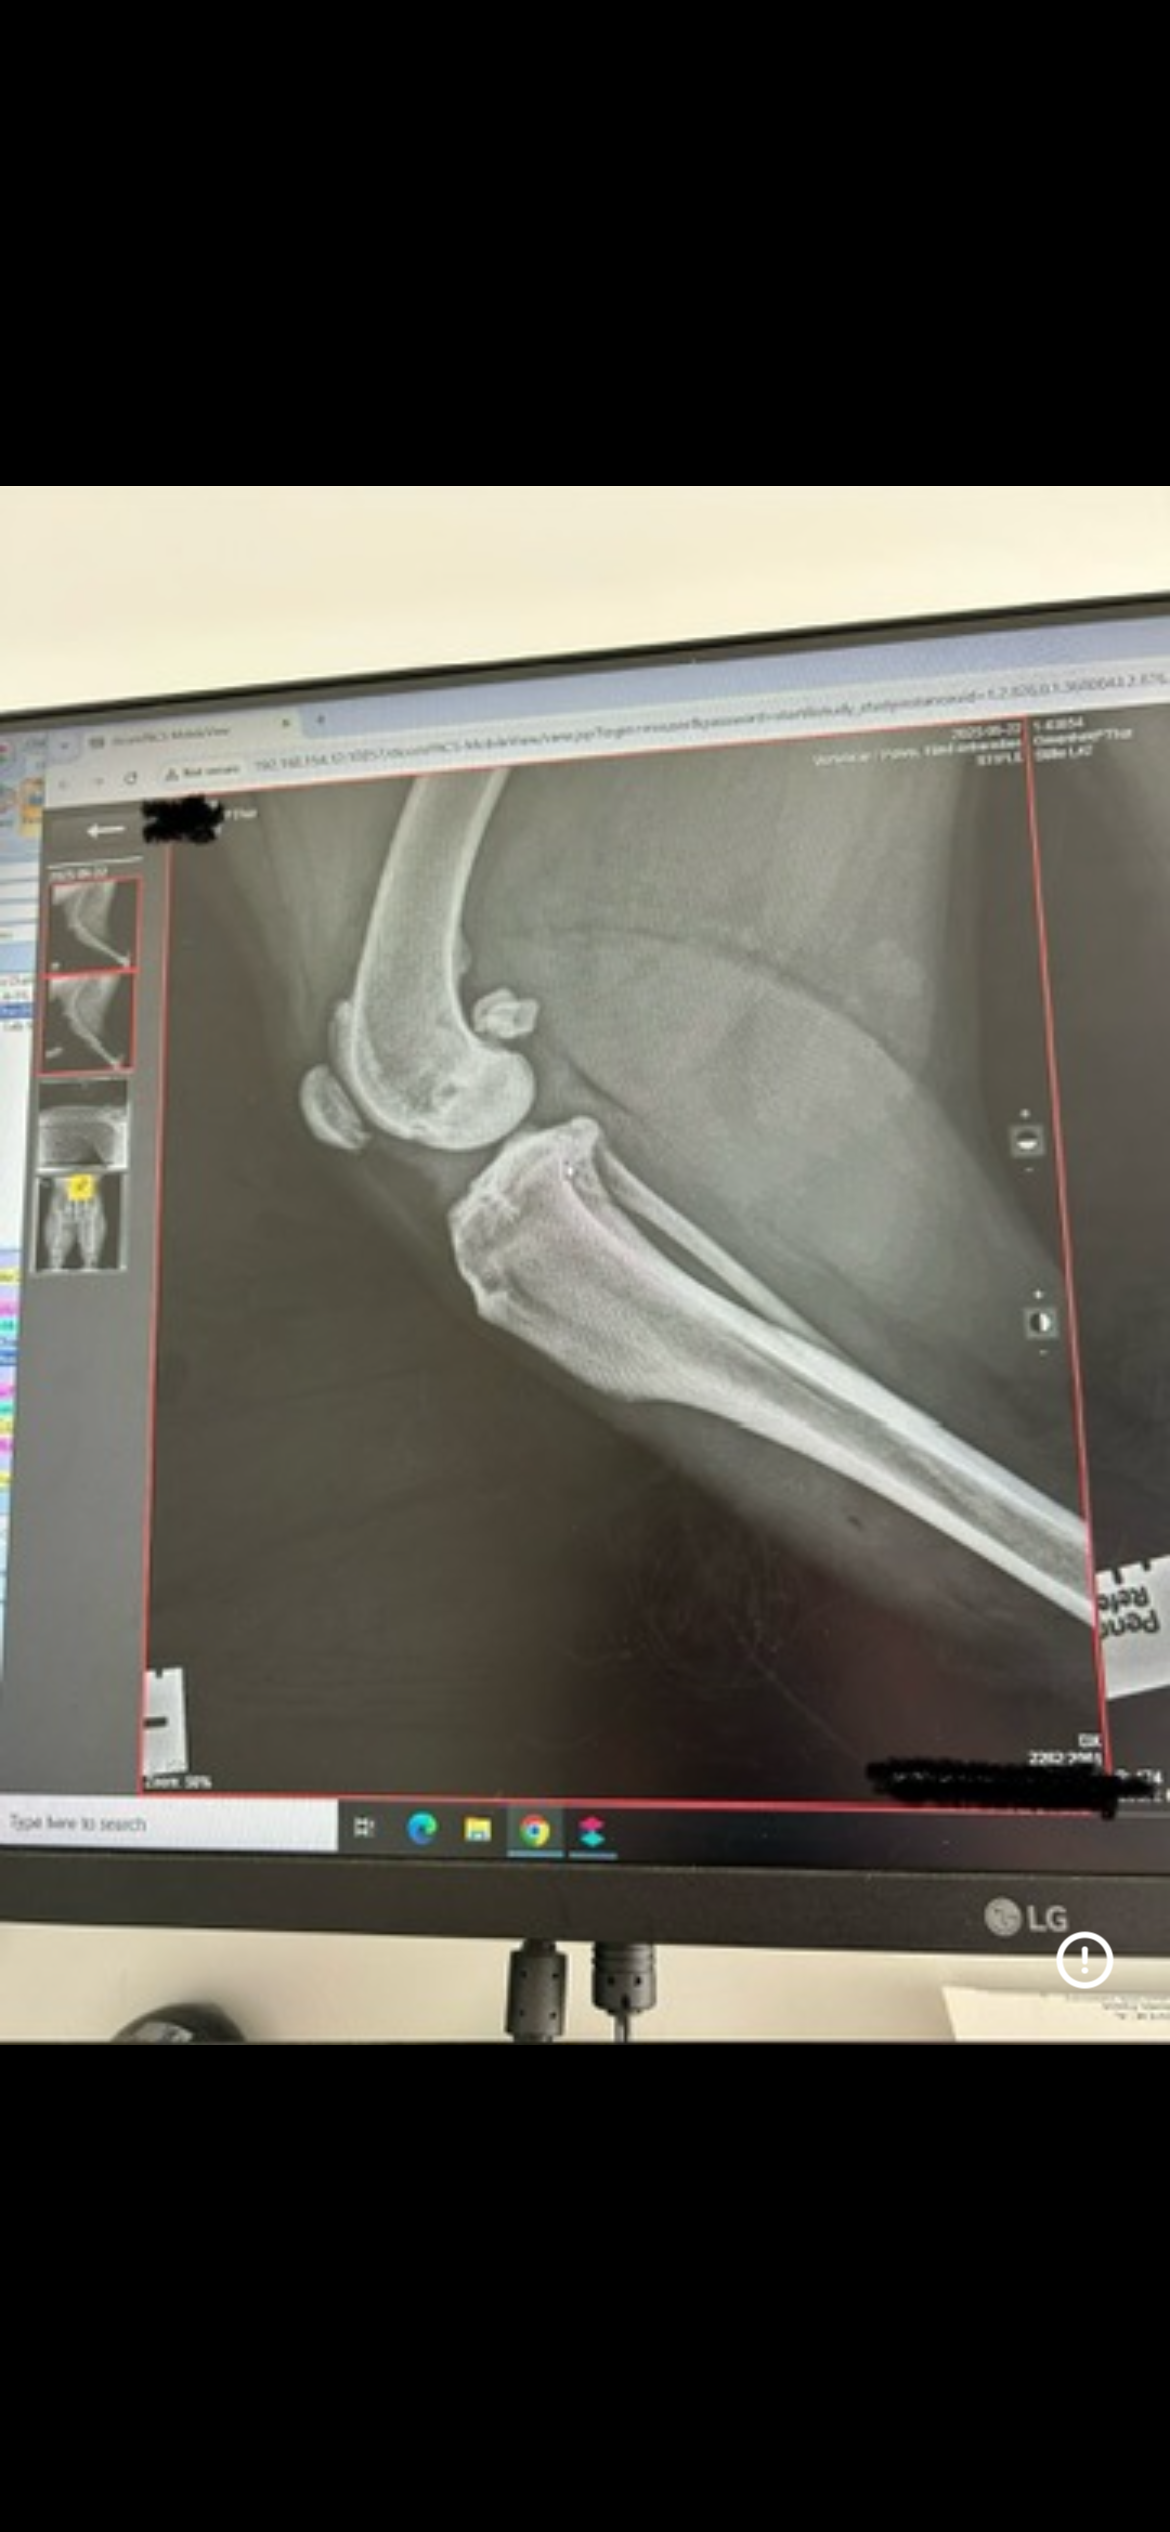

I have hip dysplasia and osteoarthritis, and my x-rays showed that the ligament in my left back leg is torn. The vets said that without TPLO surgery, I will never be able to walk properly again.